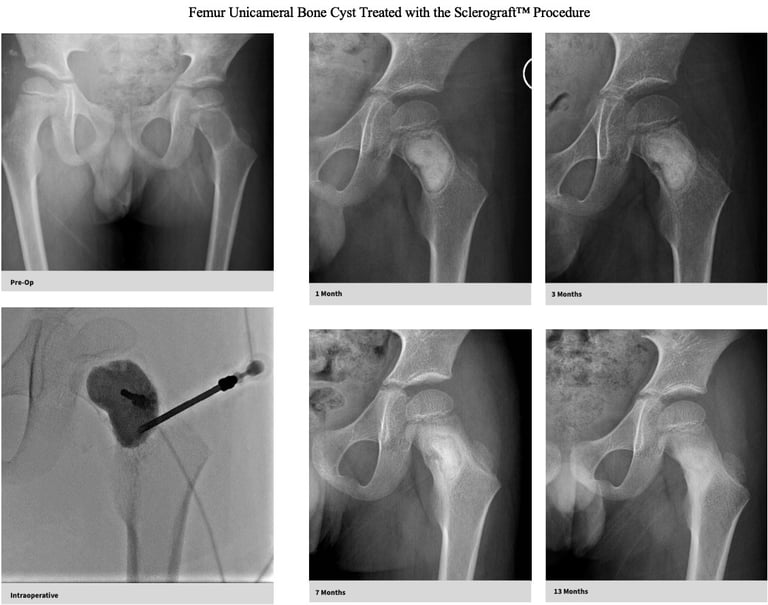

The Sclerograft procedure is a minimally invasive outpatient procedure used to treat bone cysts.

Utilizing needles, chemical sclerosis destroys the cyst wall and regenerative bone graft is injected via the needles to expedite bone healing.

The doctor uses imaging guidance (like X-ray or ultrasound) to guide needles into the cyst.

Chemical sclerosis using chemicals like doxycycline are washed through the cyst to kill the cyst wall lining

Regenerative bone graft is then injected through the needles and the needles are removed. The bone graft is temporary and is eventually reabsorbed by the body.

Gallery

Explore our educational resources and images